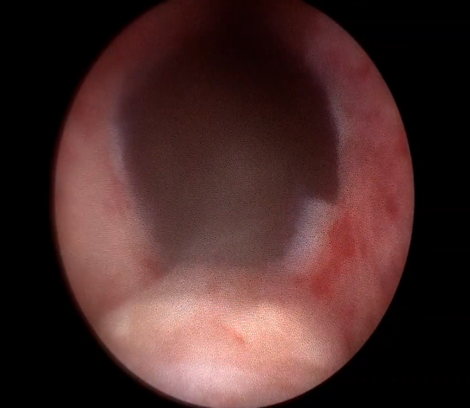

수술 전 후 전립선 요도

수술 전 비대조직으로 막힌 전립선요도

수술 후 3개월 뒤 잘 열린 전립선요도